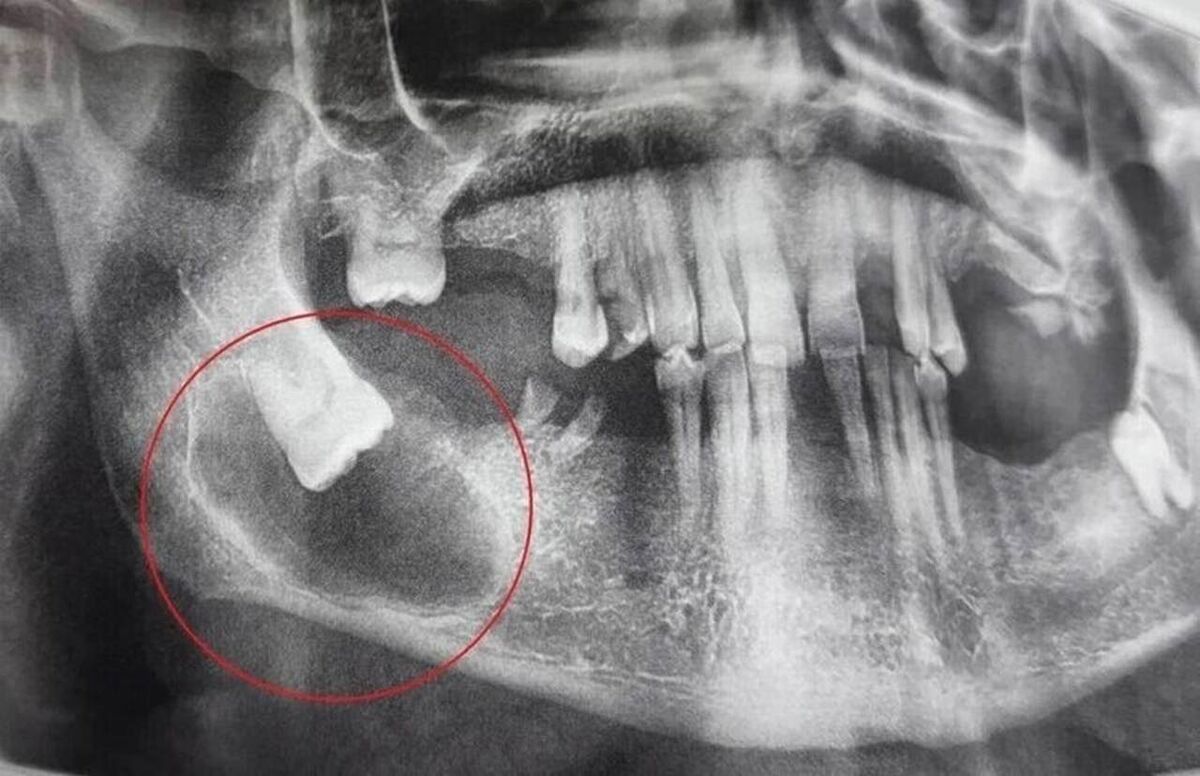

Детальная диагностика подтвердила, что зуб мудрости остался в кости, заняв горизонтальное положение. Вокруг его коронки и части корня сформировалась фолликулярная киста, которая постепенно разрушала костную ткань челюсти.

Пациенту было назначено хирургическое удаление. Операция, проведённая стоматологом-хирургом Анастасией Асеевой под местной анестезией, включала в себя удаление зуба мудрости, кисты и патологически изменённых тканей.